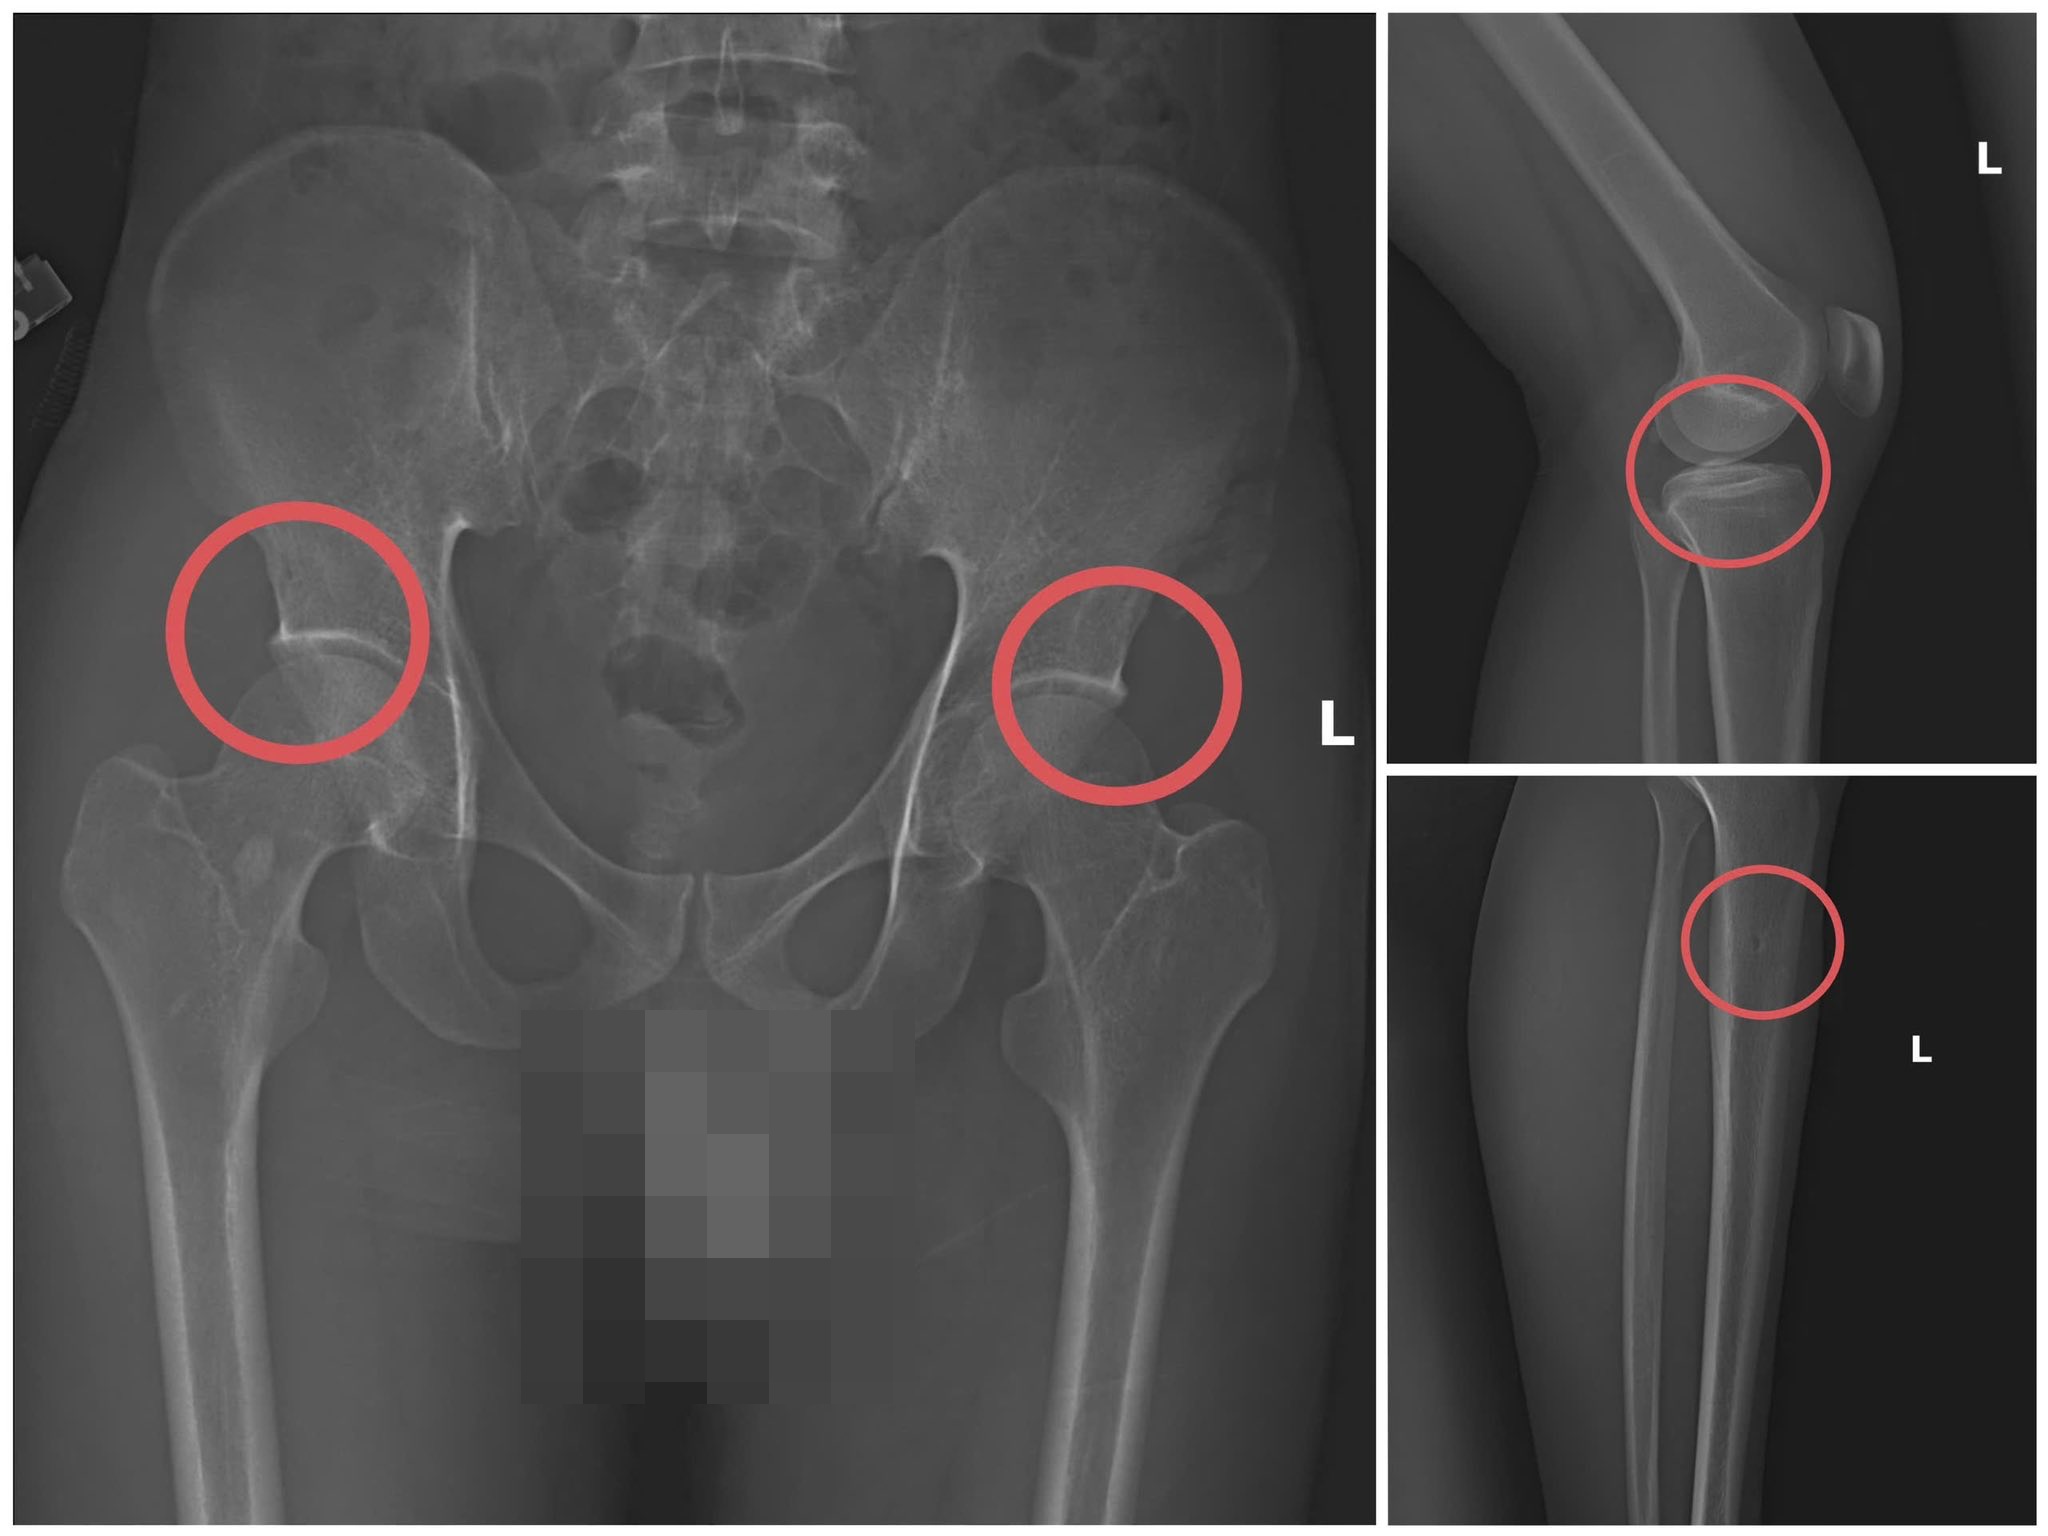

Đáng chú ý, Châu trực tiếp thực hiện hành vi tiêm thuốc mê, rồi dùng kim tiêm, búa, đinh để tác động vào xương người mua bảo hiểm, tạo nên các vết nứt, vỡ xương tương tự tai nạn thật. Khi thương tích đã tạo xong, Châu tiếp tục hướng dẫn các đối tượng dựng hiện trường giả như điện giật ngã, trượt chân ngã suối nhằm hợp thức hóa bệnh án và hoàn thiện hồ sơ yêu cầu chi trả.

Theo đánh giá của Giám đốc Công an tỉnh Phú Thọ, thủ đoạn này vừa tàn nhẫn, vô nhân tính, coi thường sức khỏe, tính mạng của người tham gia, vừa được tính toán kỹ để gây thương tích đúng vị trí có mức chi trả cao, khiến các công ty bảo hiểm khó phát hiện dấu hiệu gian dối.